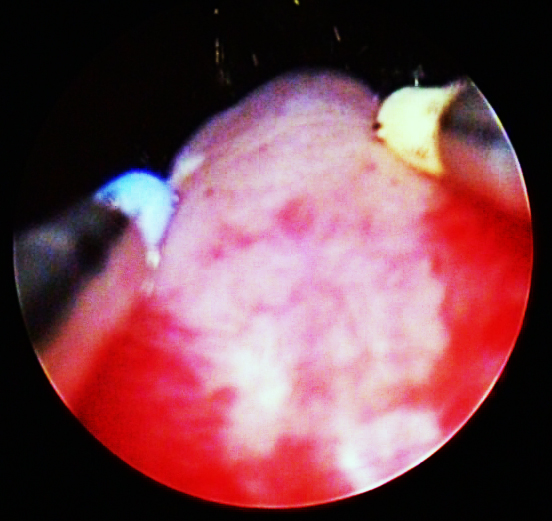

卓育敏:经尿道前列腺等离子电切术

经尿道前列腺电切术